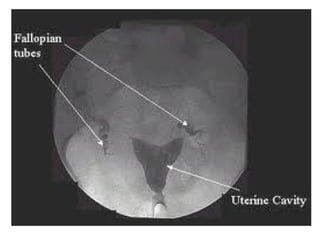

(A) normal tubal patency, (B) endometrial polyp,

(A) normal tubalpatency, (B) endometrial polyp, (C) submucosal leiomyomata, (D) intrauterine synechiae, (E) hydrosalpinges, and (F) salpingitis isthmica nodosum

• Spot radiograph clearlydepicts the interstitial, isthmic, and ampullary portions of both fallopian tubes